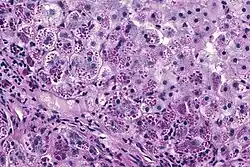

De meest voorkomende vorm van AAT-deficiëntie is ten gevolge van de Z-variant. Homozygote PiZZ-personen hebben 3-7 µmol/L AAT in hun bloed terwijl een minimum van ongeveer 11 µmol/L noodzakelijk is om de longen te beschermen. Emfyseem ontwikkelt zich bij de meeste personen met een serumconcentratie lager dan 9 µmol/L. Deze personen maken dus veel kans om reeds op jonge leeftijd emfyseem te ontwikkelen. De fout geconfigureerde AAT hoopt op in de levercellen en veroorzaakt onherstelbare schade zoals cirrose. Een biopsie van de lever zal in dat geval kenmerkende PAS-positieve granules aantonen.